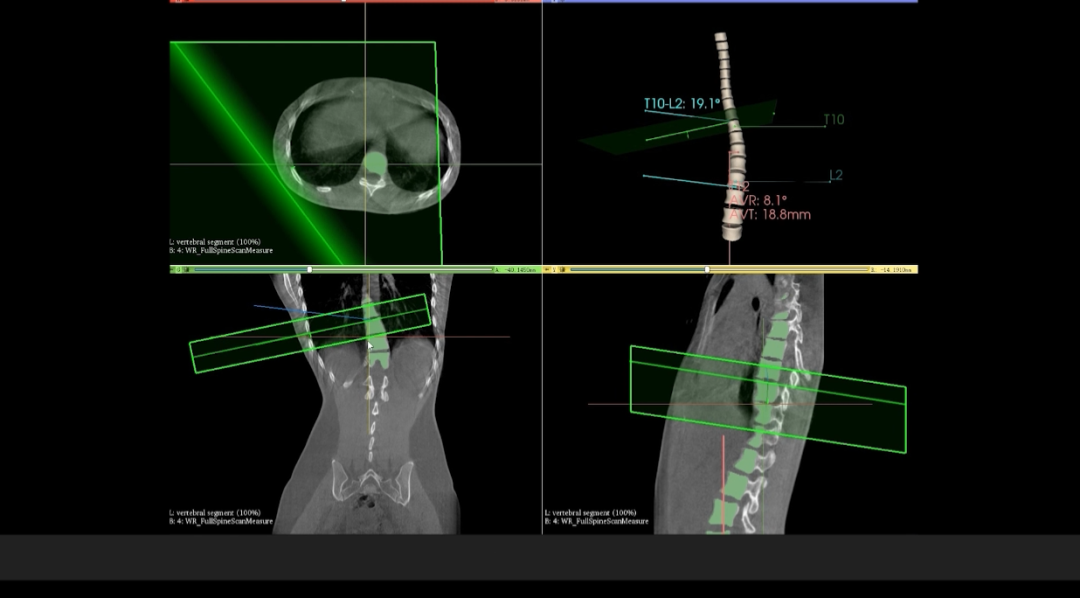

在与华西医院开展的技术合作中,WR-3D的立位脊柱三维摄影技术能提供更加丰富的临床信息,通过WR-3D的三维全脊柱扫描与重建,即可完成脊柱三维影像重建,无需进行角度拼接,消除二维Cobb角度测量的误差,可以实现包括Cobb角、前/后凸角、椎体偏移/旋转向量图、椎体旋转角条形图、矢/冠状面垂直轴偏距数据的自动测量;这项技术将为脊柱矫形的临床诊断带来从定性到定量的转变,提供丰富的数据和图表,为临床尤其是手术方案的规划制定提供非常精准的定量化数据支撑,不仅可以对脊柱冠状面参数进行精准的定量评估,还可对矢状面包括,颈椎前凸、后凸、腰椎前凸和后凸进行非常精准的评估。